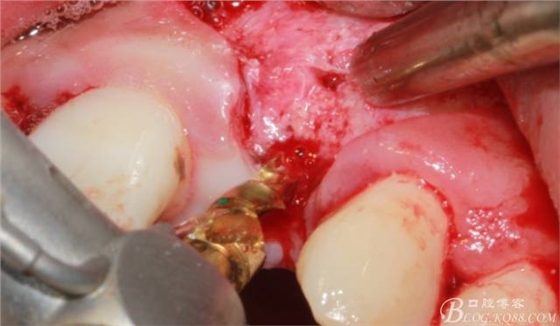

于是我果斷告知患者,手術(shù)失敗了,不能拖延,如不及時(shí)處理,炎癥繼續(xù)發(fā)展會(huì)很快波及鄰牙牙槽骨?;颊呓邮芪业慕ㄗh。切開(kāi)翻瓣,骨粉及生物膜消失了,骨吸收嚴(yán)重,幸運(yùn)的是,因?yàn)樘幚砑皶r(shí),鄰牙骨支持依然存在。

徹底掻刮。